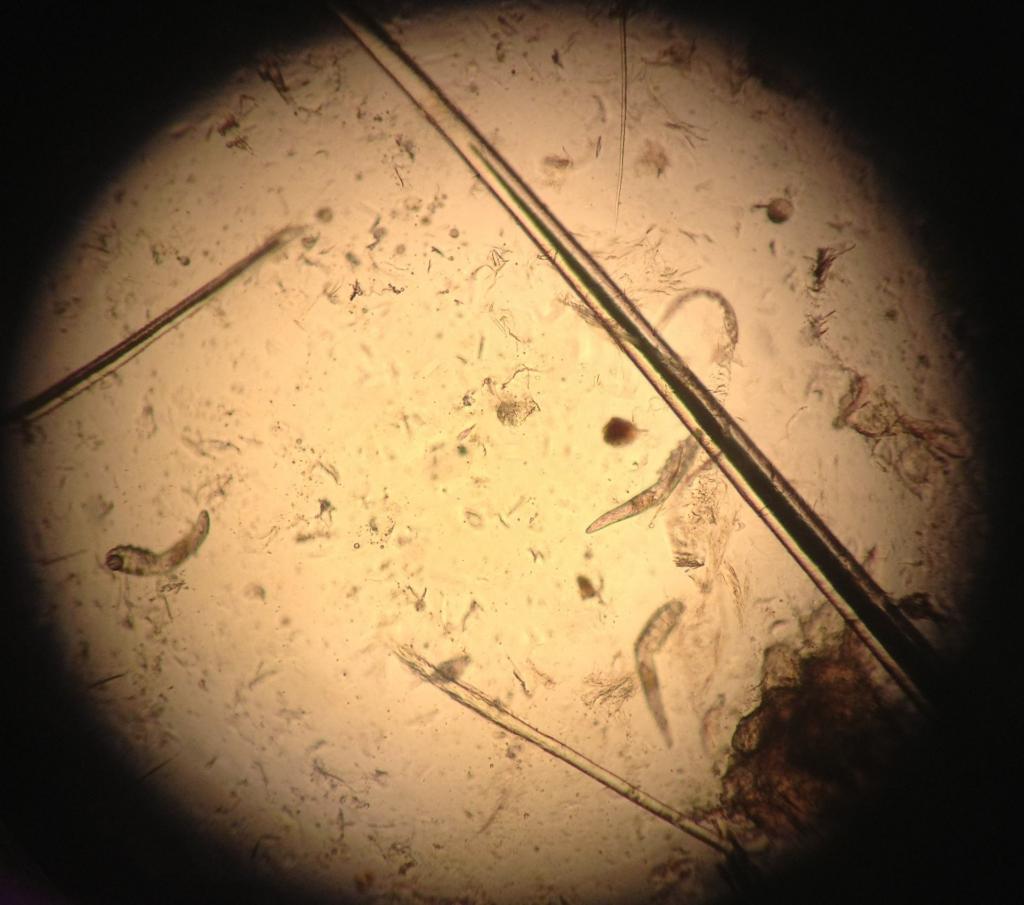

Анализ на клеща демодекс делается просто и безболезненно. Специалист берет соскоб кожи лица или волосяного покрова (брови, ресницы) и отправляет его на исследование в лабораторию. Далее проводится его изучение под микроскопом. Именно так можно увидеть полупрозрачных паразитов и результаты их жизнедеятельности.

image